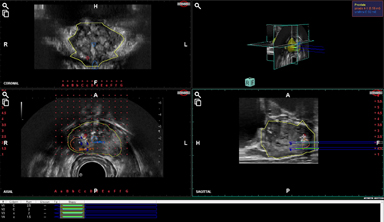

Needle Pre-planning Rendering

Navigation of Target Biopsy